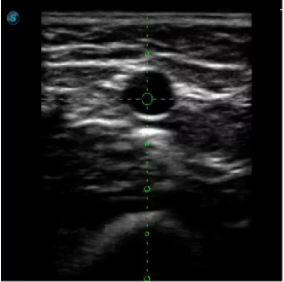

4  置管專用探頭

實(shí)時觀察穿刺針進(jìn)入血管的全過程,方便操作及較短的穿刺路徑,智能進(jìn)針尺寸提示,讓置管工作更加輕松,高效。

不同進(jìn)針路徑